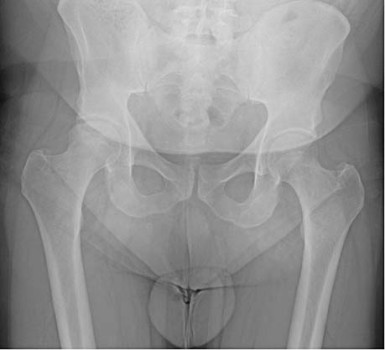

De orthopedisch chirurg vond bij het onderzoek van de knie geen bijzonderheden. Bij onderzoek van de rechterheup viel op dat met name de endorotatie beperkt en pijnlijk was. Röntgenfoto’s van de rechterheup toonden aanwijzingen voor een avasculaire femurkopnecrose met secundaire coxartrose [figuur 1]; een MRI bevestigde deze diagnose [figuur 2].

De patiënt kreeg een totale heupprothese, waarna hij snel herstelde. De knieklachten verdwenen en hij kon weer aan het werk. De femurkop werd ingestuurd voor pathologisch onderzoek, dat het beeld bevestigde van subchondrale avasculaire botnecrose met onderliggende osteoporose, hetgeen kan passen bij prednisongebruik.